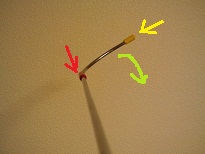

そこで、以前から作りたいと思っていた物を昨日作ってみました!

カインズホームで、S字フック98円、ビニールテープ28円X2色で、計154円。

S字フックを切断して、曲げて、ビニールテープを張り付けると、

こんな感じ。

実際には、長いほうの先を目の下に当てて、

赤のテープを見ていて頂いても、黄色も認識できますが、

指の時と同じように、ゆっくりと回すと、

赤を見ていると、黄色が見えなくなります。

大成功です。指でやるときよりも、赤とか黄色とかの指標をしっかりと作る方が、目がきょろきょろしないようです。

150円で作った、この棒。

名前は「栗棒:クリボー」と名付けよう。